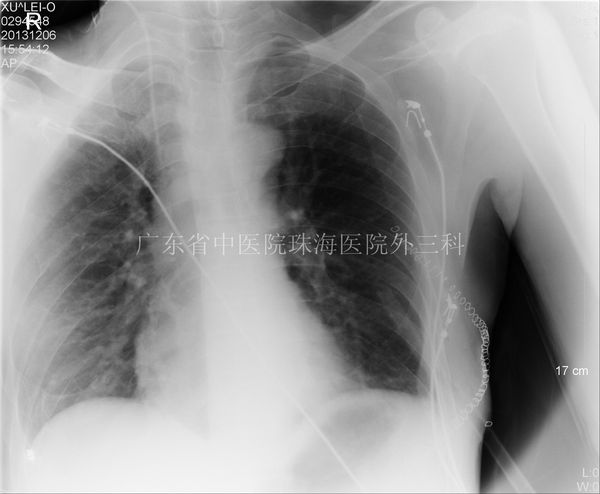

胸片胃泡大

胸片胃泡大,

胸片表现包括外高内低的弧形影及肋膈角变钝;支气管血管纹理消失;以及

周世明8lfkx6km 馆藏分类肥胖症胃部分切除术后患者,胃泡未见显示.

外伤嵌顿性膈疝救治案例